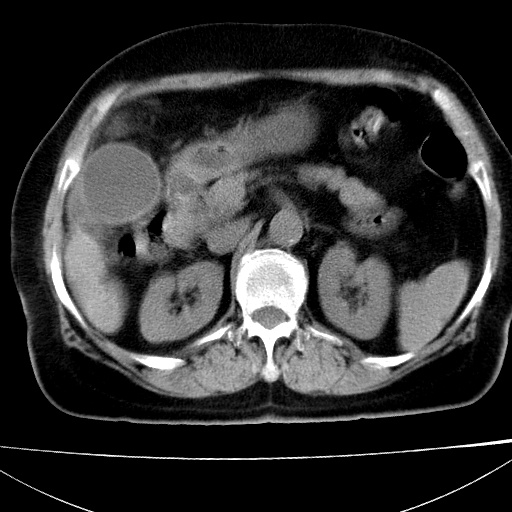

患者女74岁;右上腹胀痛1月,伴恶心,无发热;生活在疫水区。有术后病理及术后半年的追踪ct.

1)慢性血吸虫病(典型)。2)肝硬化。3)肝癌?4)胆囊炎。5)少量腹水。6)右侧少量胸腔积液。

肝脏体积缩小,肝裂增宽,边缘不平呈波浪状,肝右叶见分隔状条索形钙化,亦见多结节低密度灶,边界不清,肝周可见少许液性暗区,胆囊增大内密度均匀,脾脏下缘低于脏脏的下缘,胸腔亦见液性暗区,余未见明显异常.

诊断:1肝硬化并慢性吸血虫病,脾肿大

2肝内占位,考虑肝癌可能性大,建议做增强

3胆囊炎, 4少量腹水及胸水

病人以胆囊癌手术的,病理结果为中分化腺癌。

现在看看肝右叶内圆形低密度影你们考虑什么呢?

肝内圆形低密度影考虑扩张的胆管

请看3mm重建像如下: